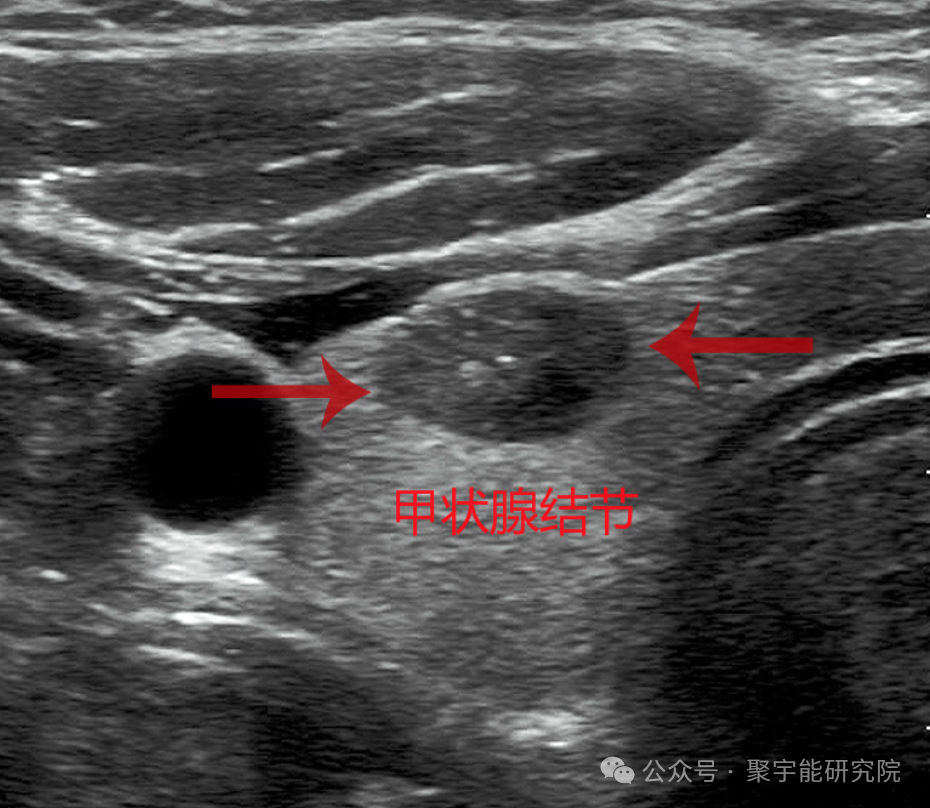

在各项体检异常中,比较常见的就是各种结节了,尤其是甲状腺结节、乳腺结节和肺结节最为高发,在女性中更为常见。

甲状腺结节在各个年龄的人群中均可见到。在成人群体中,以体检方式统计的发病率为5%~7%,以超声检查方式统计的发病率为20%~76%(该结果监测的人群相同)。女性多于男性,男女之比约1:3.83。